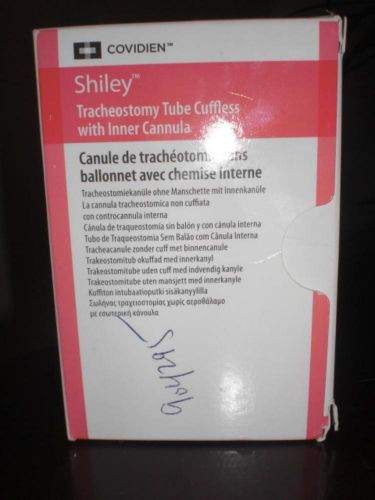

COVIDIEN SHILEY TRACHEOSTOMY TUBE CUFFLESS WITH INNER CANNULA 6CFS 6.4mm I.D